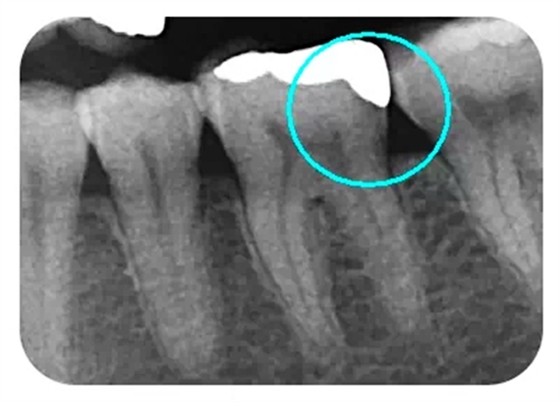

從下面這張X線中可以看出,嵌體遠(yuǎn)中邊緣沒有懸突,與牙體邊緣密合相接。